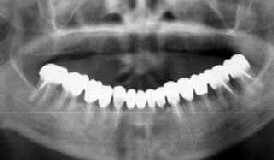

| 36歳 女性 | 術後12年<48歳) |

| 初診時 パノラマ | 恐がり屋さんでメインテナンスに全く応じない患者さんですが… |

経過:

術後月1度のメインテナンスを約束し、不定期ながらも4年間はメインテナンスを継続したが、

その後勤務先の変更もあり、度重なる催促にもかかわらずメインテナンスを中止。

術後7年目に左側上顎ブリッジの動揺を主訴に来院し、│7を抜歯(歯槽骨破壊の進行のため)

。再度メインテナンスの重要性を説明するも再び来院せず4年を経過。

今回、右側上顎ブリッジの動揺を主訴に再び来院。前回同様74│を抜歯し、義歯装着を

予定している。

考察:

74│7の歯槽骨破壊が予想通り著明である反面、それ以外の歯は動揺もなく今後比較的

長期間の保存が見込まれる。Fop+HAP を行った前歯部も経過は比較的良好である。歯周外科処置

の可否を考える上でも貴重な症例である。当時の技術水準を考えるとやむをえないことではあるが、

全顎歯周外科処置を行い、咬合の再構成を施した上でフルマウスのブリッジをしていれば更なる

歯牙の延命が可能であったものと思われる。

感想:

「歯がグラグラしだしたので…」と電話を受け取った時には、長年放置されていたことでもあり、

さぞやひどい状況になっただろうと想像していたが、口腔内を拝見して一安心。

初診当時36歳で、ほとんどの歯を抜歯されても不思議のない状況だった患者さんが、12年の歳月を

経て17本の残存歯があることには感心した。反面、今流の処置を施し、メインテナンスも十分に

行えたら更なる延命効果が期待できるものと残念な気持ちも同居する。